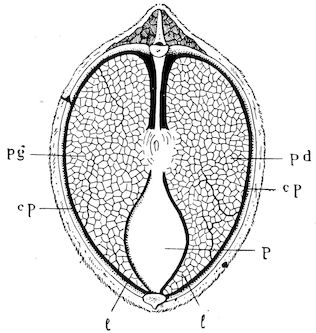

Fig. 1.—Rachitis in a young goat.

Rachitis is a disease of youth, and is common both to the human species and to all domestic animals. It is characterised by irregularities in development and by imperfect consolidation of the bones. The boundary between rachitis and osseous cachexia is difficult to define and in fact at the present moment the two diseases can scarcely be defined with exactitude. Rachitis again is often complicated with softening of the bones, disease of the limbs, arrested development, etc., but it must not be forgotten that although the irregularities in ossification and development of the skeleton are the symptoms most striking to the eye, they do not stand alone, and that from the point of view of development all the tissues, including the muscles, are more or less affected and that most of the physiological functions such as digestion and the secretion of urine are deranged.

Symptoms. The onset is absolutely insidious and the diagnosis of rachitis is never made until nutrition has long been abnormal.

This disturbance of nutrition is revealed by irregularity and abnormality in appetite, by difficulty in rising and moving about, and by the animals lying down for long periods. The subjects are feeble, sluggish and badly developed.

Next supervenes the second phase characterised by deformity of bones. This is of two kinds—deformity in the neighbourhood of joints (deformity or enlargement of the epiphyses) and deformity of the diaphyses. The former results from irregularity in ossification of the articular cartilages. The latter is followed by loss of rigidity in the bones of the limbs which, under the influence of the body weight and of muscular contraction, bend in different directions.

The bones appear of increased thickness principally towards the 6articulations. The latter are deformed, and on palpation are found to be surrounded by uneven and irregular growths.

The front limbs are distorted. In young pigs, lambs, and less frequently in foals, calves and dogs, the jaws become deformed, and mastication is rendered difficult.

The vertebral column may also be affected, and lordosis (bending downwards of the back) or skoliosis (lateral bending of the back) is somewhat frequent.

Cyphosis, or upward bending of the back, seldom occurs, and when seen, sometimes results from disease other than rachitis.

General development is always interfered with and the young creatures are generally dwarfed.

The digestive apparatus is disordered, the appetite is irregular and sometimes depraved, while indigestion, gastritis, and enteritis are not exceptional. Physiological and pathological research has shown that the quantity of phosphoric acid eliminated in twenty-four hours in a rachitic child is double the quantity passed by a healthy infant. The amount of urea in the urine (which is a criterion of nutrition, and usually varies in proportion to the amount of food ingested) is, on the contrary, diminished even when highly nitrogenous food is given, thus suggesting diminution in nutrition.

Lesions. The lesions are represented by abnormal and irregular thickening around the interarticular cartilages. The cartilage is thickened, compressible, very spongy and without regular ossification. Diffused periostitis exists principally towards the extremities of the bone. Beneath the periosteum the surface of the bone appears rough and softened. On section the medullary canals are seen to be enlarged and filled with marrow of a gelatinous character. The Haversian canals are dilated, and the entire tissue appears very vascular. Chemical analysis proves that the mineral constituents of the bone, particularly the phosphates, have diminished by one-half; the organic constituents on the other hand are increased in a similar ratio, but the ossein is abnormal. Ossification has, in a word, been incomplete.

7Diagnosis. Diagnosis presents no difficulty except in the early stages before deformity has occurred.

Rachitis can scarcely be mistaken for any other condition except perhaps infectious rheumatism, but the rapid course of the disease in the latter case, the persistence of fever and the swelling of the joint cavities sufficiently differentiate the conditions provided care is exercised.

Prognosis. From an economic point of view the prognosis is very grave for if the lesions are extensive there is nothing to be gained by keeping the animal.

Treatment. Treatment differs very little, whether the animals are still being suckled or have been weaned. In the former case it is necessary to improve the quality and chemical constitution of the mother’s milk by giving food, richer both in mineral salts and in nitrogenous material.

Cooked grains, milk, and forage of good quality should be given freely. When the mothers are exhausted and anæmic it is better to feed the little animals artificially or to change them to a foster-mother. Those already weaned should be given good rich milk, eggs, boiled gruel, and drugs, such as the phospho-chlorate of lime, 1 to 1½ drachms per day (for a calf); lacto-phosphate of lime, 1 to 1½ drachms; bi-phosphate of lime, 1 drachm, or simply ordinary phosphate of lime. Oil containing 1 per cent. of dissolved phosphorus may be given in doses of 1 to 2½ drachms, according to the size of the calves, but its use calls for much care, and it should only be given for alternate periods of a fortnight. The glycerophosphates are not very active. Beef meal in doses of 6 drachms to 1½ ounces and chloride of ammonium in doses of 30 to 60 grains have also been used advantageously. The above drugs, but particularly the bi-phosphate of lime and chloride of ammonium, stimulate nutrition and diminish the quantity of phosphoric acid eliminated.